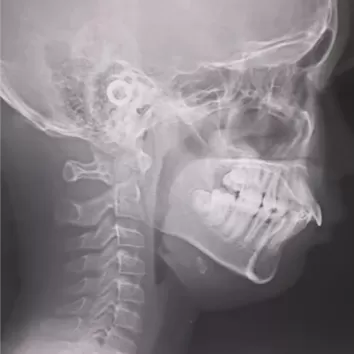

X-rays before treatment

[Panoramic Radiography/Lateral Cephalogram]